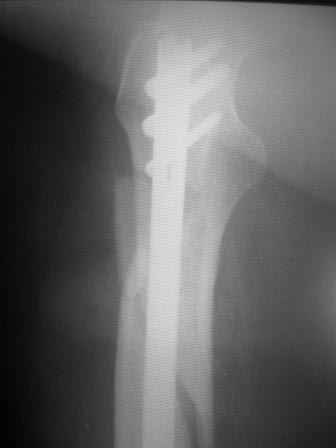

Re: проксимальный отдел бедра

Уважаемый Максим, поддерживаю Вашу тактику на сто процентов. Более того скажу, что было в моей практике: установка блокированного бедренного стержня под местной анестезией (инфильтрационной), больная инвалид первой группы-анестезиологи отказались от больной. Выписана из отделения через 10-ть суток с объёмом движений до перелома (обслужи себя сам). Автору поста, чем меньше продержите до операции, тем лучше эфект от лечения (но без фанатизма).